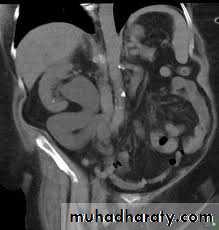

CTTreatment

UPJ obstruction may also occur in either the upper or the lower half (usually the latter) of a duplicated collecting system,or of a horseshoe or ectopic kidney.